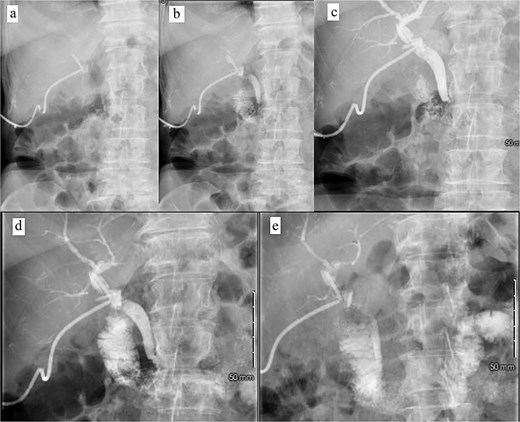

Patient was brought to the OR, induced, and the peritoneum was accessed via optical view trocar. After the critical view of safety was obtained, the cystic duct was partially transected and a 6-French ureteral catheter was threaded through the duct and into the CBD. Initial cholangiogram showed complete obstruction of the distal CBD. A 0.035 guidewire was advanced through the ureteral catheter. The ureteral catheter was then exchanged for a 9 × 40 mm long vascular balloon catheter. The balloon was then centered at the ampulla of vater and inflated to its nominal pressure for 5 min. A small indentation was noticed at the level of the ampulla once the balloon was fully insufflated, as expected. The completion cholangiogram showed prompt evacuation of contrast into the duodenum. However, numerous “floating” filling defects continued to be present (Fig. 4). The decision was thus made to leave a T-tube in place via a 1-cm longitudinal choledochotomy. The incision was reapproximated around the t-tube with interrupted 4–0 PDS. The vascular balloon catheter was removed, the cystic duct was completely transected, and the gallbladder was dissected off the liver bed.

Intraoperative cholangiogram. (a) Initial cholangiogram via 6-fr ureteral stent showing multiple filling defects (arrows). (b) Guidewire passed through the ureteral stent and down to the level of the ampulla of vater, demonstrating complete CBD obstruction. (c) 7 × 40 mm vascular catheter balloon advanced over the guidewire and through the ampulla of vater. Dilated to nominal pressure. (d) Contrast now able to leave the CBD and into the duodenum. Residual “floating” filling defects still seen (arrows). (e) Vascular catheter exchanged for a 9 × 40 mm balloon and dilated to nominal pressure. (f) Completion cholangiogram shows brisk outflow of contrast with residual filling defects (arrows).